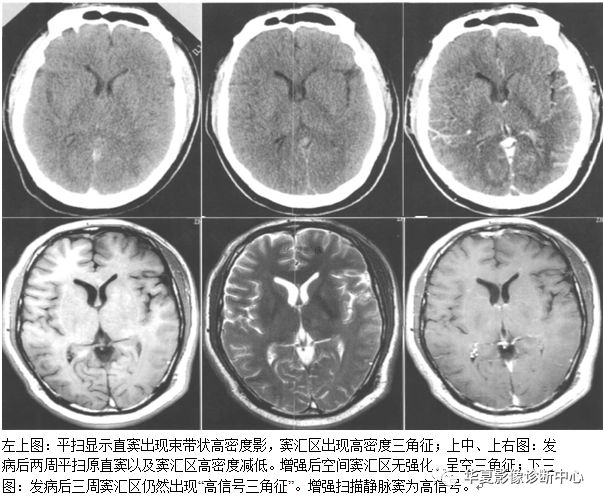

十三、空三角征:

在CT或MRI增强图像上,在多个连续的横断CT或MRI图像上表现为上矢状窦三角形增强或高密度区域内出现相对低密度区。空三角征为矢状窦血栓形成时颅脑增强CT或MRI的常见征象,出现率约为35%,表现为强化的三角形环即中心低信号周边为三角形高信号,位于上矢状窦区。矢状窦邻近有血管丛,为血栓形成后的侧支循环。目前对该征病理生理的解释并不一致,包括以下假说:1)静脉窦内血栓再通。2)栓子机化。3)血脑屏障破坏。4)硬膜外和硬膜侧支静脉的扩张。有认为最合理的解释为硬膜血管的强化,为所在区域的血管网(硬膜海绵间隙)和脑膜静脉属支的强化,中心低密度为栓子。国外学者认为血栓形成的主要原因有3个:1)血管易于血栓形成,包括原发性和遗传性疾病。最常见为继发性凝血酶原激活如妊娠;血液或系统性疾病如红细胞增生症、系统性红斑狼疮、恶性肿瘤、脱水导致血液浓缩,药物如避孕药或化疗药如L一天门冬酸胺酶。2)血流障碍如肿瘤、心衰、动静脉痊。3)静脉窦壁的炎症、感染、纤维化或损伤,如:静脉窦炎、外耳炎、乳腺炎和创伤。l/4的病人查不到原因。矢状窦血栓形成的临床表现有头痛、视乳头水肿等。急性脑静脉窦血栓形成往往存在比较典型的表现,可见上矢状窦区三角形以及横窦区条索状高密度影,是脑静脉窦内新形成血栓病变早期的直接反映;临床上虽然脑硬膜窦血栓的发病率较高,不过单纯大脑浅静脉及深静脉部位的血栓形成较少;CT增强显示空三角征或条状充盈缺损,特征明显,对急性和亚急性患者有重要意义。CT平扫亦可显示由于静脉淤血、静脉性脑梗死以及脑脊液重吸收障碍引起的病理征象,如对称或弥漫性脑肿胀、多灶性脑出血等。

MRI平扫对本病较为敏感,可显示不同时期血栓的信号,而正常静脉窦的留空信号则消失。急性期T1WI为等信号,与留空信号较为接近,T2WI为低信号,由于信号特征较不明显,因此MRI不易诊断;亚急性期T1WI、T2WI均为明显高信号,容易确诊;慢性期各脉冲序列血栓信号减低,常常出现假阳性。但是可通过与CVST引发的脑水肿、脑梗死、脑积水等间接征象相结合,以辅助诊断。